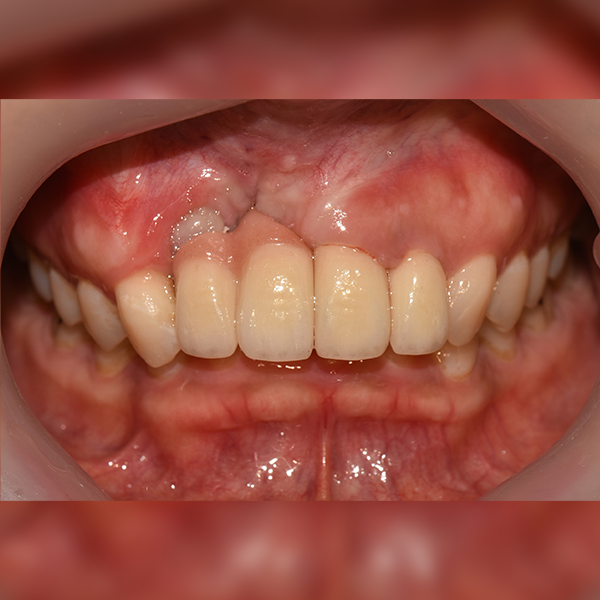

상악/앞니 부분 / 3개이하 / 뼈이식

症例.111 30代 趙*善 2018-11-30 / 2019-12-10

Before Before

After After